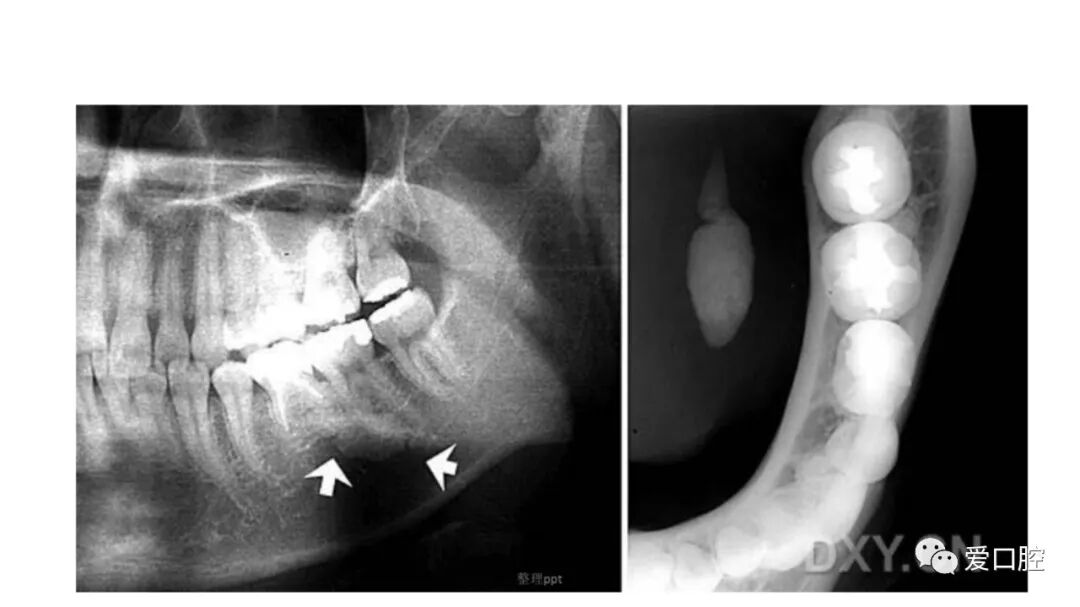

口腔小技巧 | 口腔科常见的病例影像!